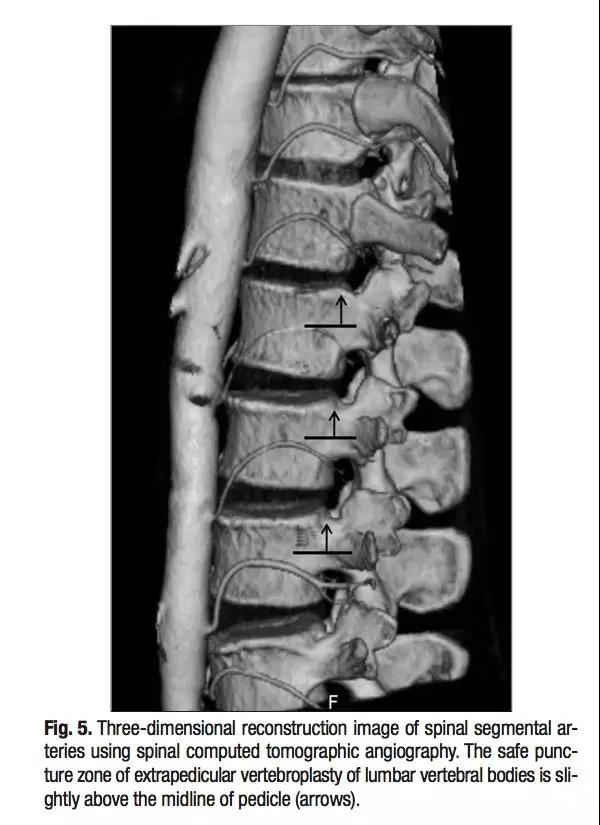

椎弓根外侧入路不走椎弓根,走椎旁。不伤神经,却有可能伤及椎旁节段血管。

三维CT显示椎旁节段动脉就在椎体旁正中走行,所以椎弓根外侧穿刺安全边界在椎弓根中线以上。